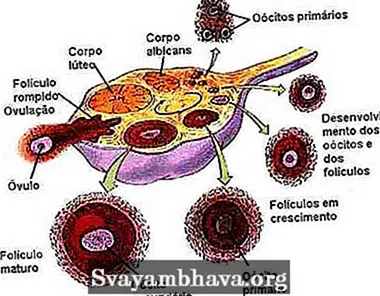

Созревание фолликула в яичнике: этапы и процессы

Раздел: Другие животные